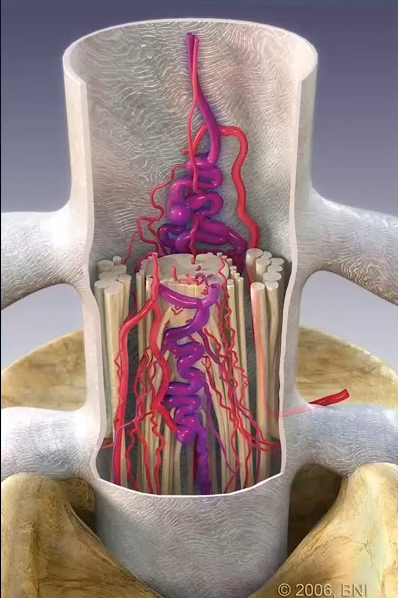

Dr. Choudhri has specific expertise in the resection of challenging brainstem cavernous malformations, utilizing CO2 laser technology, neuronavigation, and continuous neurophysiological monitoring to remove these lesions while preserving the delicate brainstem pathways. He published early work on the flexible omnidirectional CO2 laser for resection of brainstem, supratentorial, and intramedullary cavernous malformations during his training at Stanford.

Brainstem cavernous malformations are among the most technically demanding lesions in neurosurgery. Dr. Choudhri has published peer-reviewed studies on techniques including endoscopic-assisted approaches and gravity-retraction positioning strategies to safely access these deep-seated lesions.